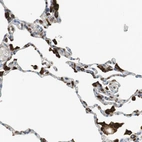

Immunohistochemical staining of human lung shows strong granular cytoplasmic positivity in macrophages.